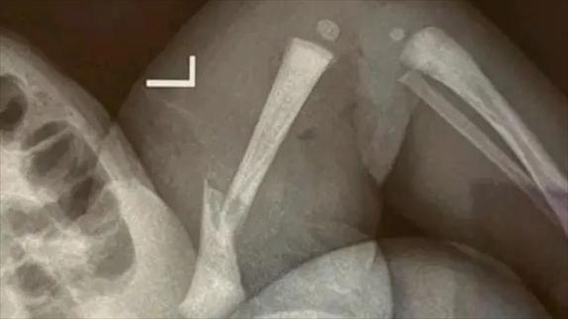

·江蘇靖江新生兒骨折家長質(zhì)疑系醫(yī)療事故,靖江市人民醫(yī)院:手法不熟導(dǎo)致。